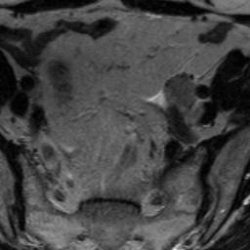

Фрагмент МРТ пояснично-крестцового отдела позвоночника: Т2 ВИ в аксиальной проекции.

Что привлекает внимание на снимке?